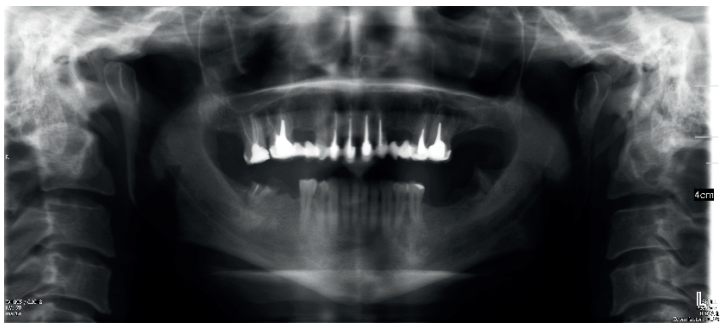

Paciente varón de 43 años, sin antecedentes médicos de interés, portador de rehabilitación protética mediante pernos intrarradiculares y coronas metalocerámicas de 16 a 26 que acude a consulta por infecciones de repetición y fístulas en sector anterosuperior y zona 25-26. El paciente desea valorar la posibilidad de mantener sus dientes, ya que el tratamiento que le han propuesto consiste en la extracción de todos ellos y colocación de implantes.

El paciente aporta como estudio radiológico una ortopantomografía (OPG), (Figura 1). Se realizaron radiografías periapicales (Figuras 2 y 3), así como exploración clínica incluyendo la valoración periodontal de los dientes afectados, sin observar profundidades de sondaje aumentadas que pudieran indicar la existencia de lesiones endoperiodontales.

Para el correcto diagnóstico de lesiones radiolúcidas a nivel periapical es importante disponer de imágenes radiológicas que muestren con precisión la situación y tamaño de dichas lesiones. En nuestro caso el paciente aportaba una ortopantomografía. Este tipo de radiografía no es adecuada para el diagnóstico en endodoncia. La radiografía periapical aporta mejor definición, especialmente a nivel anterior, ya que presenta una menor distorsión. Actualmente el CBCT es la prueba radiológica más fiable, ya que proporciona imágenes en las tres dimensiones del espacio, lo que permite diagnósticos más precisos1,2 .